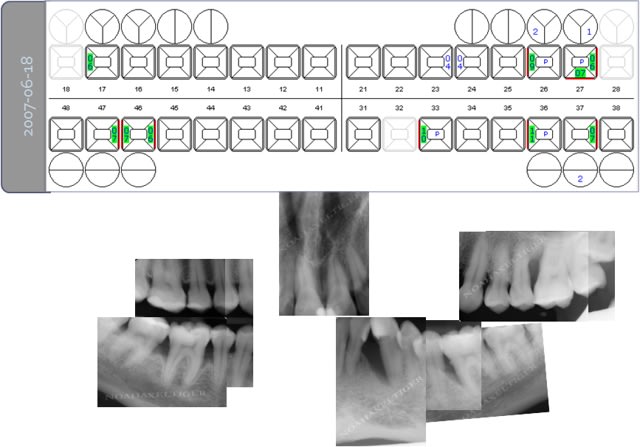

> voila comme promis les 2 cas cliniques.

>

> patiente 1 : paro aggressive, importantes lésions

> angulaires traitées par emdogain sauf mesial 33 où

> j'ai préféré faire une GTR avec comblement

> BioOss.

Superbes résultats !

1 La conservation de la 28 n'est elle pas un facteur défavorable ?

2 la 26 a t'elle été extraite en première intention ou après un échec de la régénération ?

3 avais tu dans ce cas une espèce bactérienne spécifique ?